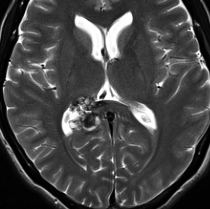

脳幹部の海綿状血管腫 brainstem cavernous hemangioma

2度の延髄内出血を生じた海綿状血管腫です。でも初回の出血からすでに27年間がたちます。症状も回復して麻痺もなくていまは社会生活に困ることはありません。脳幹部の海綿状血管腫の中には1ヶ月に何回もひどい出血を繰り返すのもあるのですが,この例のように30年近い間に軽い出血が2回だけというのもあります。残念ながら正確にこれを予測することはできません。この患者さんの海綿状血管腫は手術で摘出すれば麻痺などの合併症の可能性があるのでしません。

脳幹部の海綿状血管腫を手術した方がいいかどうかはすごく慎重に判断しないといけないのです。場合によってはとても重い後遺症が手術ででてしまうこともあります。もちろん手術ですごく症状がよくなってとても元気に暮らしている患者さんもたくさんいますが,そうでない患者さんもいるのです。手術を決意する前に,少なくとももう一人の脳外科医からセカンドオピニオンを聞きましょう。